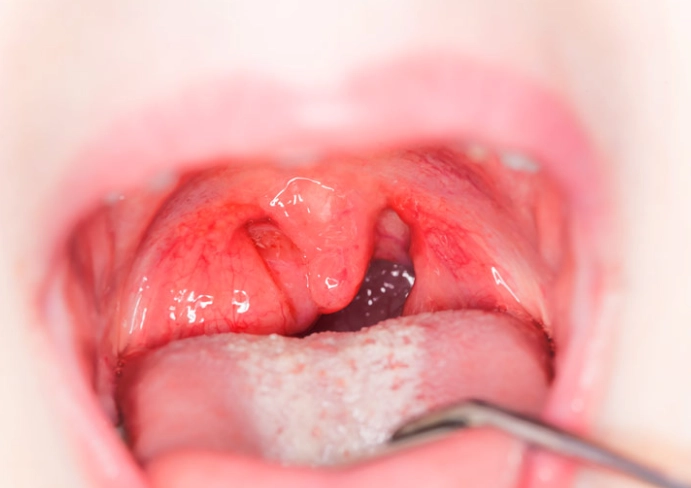

扁桃腺發炎怎麼緩解?本文提供完整的扁桃腺發炎緩解指南,從居家護理技巧到醫療治療方案,幫助你快速減輕疼痛不適,恢復健康狀態。了解有效的扁桃腺發炎緩解方法,避免併發症發生。

為什麼扁桃腺會反覆發炎?扁桃腺發炎原因究竟有哪些?本文從病毒感染、細菌感染到免疫力下降等角度,完整解析扁桃腺發炎的成因,並提供實用預防建議,幫助您遠離喉嚨不適。